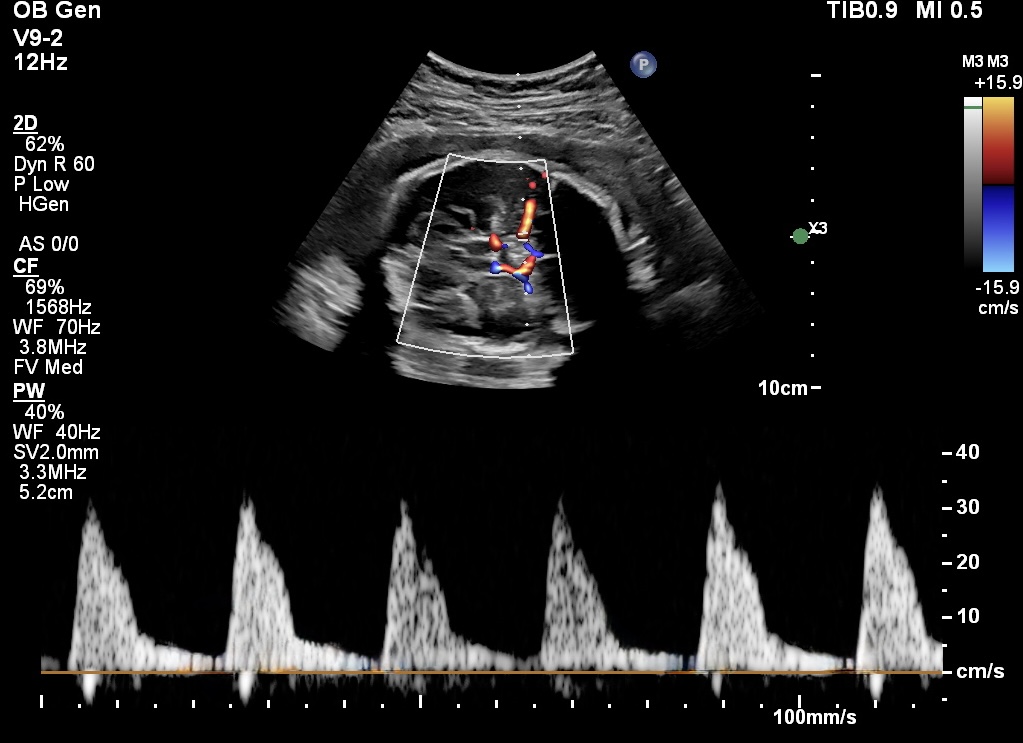

The Cerebro-Placental Ratio (CPR) is calculated by comparing the blood flow in the middle cerebral artery (MCA) to the umbilical artery (UA), giving clinicians a clear understanding of the fetus’s brain-sparing effect—the ability to redirect blood to vital organs like the brain when placental blood flow is insufficient.

It is calculated as the ratio between the pulsatility index (PI) of the middle cerebral artery (MCA) and the pulsatility index (PI) of the umbilical artery (UA).

CPR=PI-MCA/ PI-UA